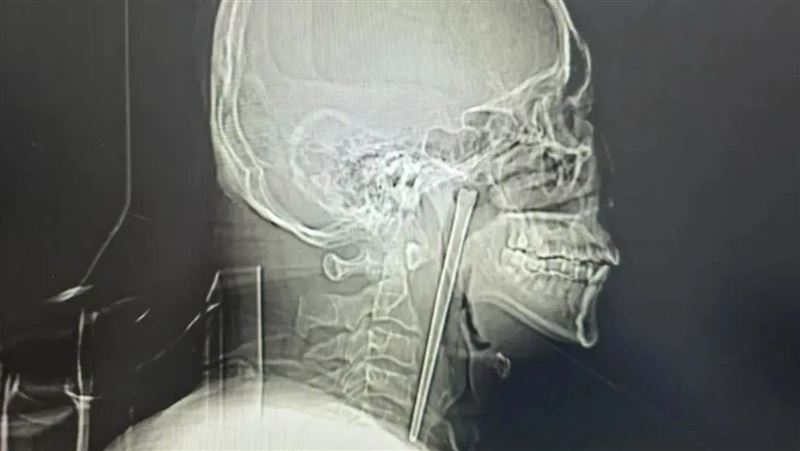

TVBS

苗栗縣2025年10月中破獲一起柬埔寨跨境運輸海洛因毒品案,檢警查出49歲蘇姓女子、46歲羅姓女子和38歲葉姓男子等3人,涉嫌接受販毒集團招待,以10到15萬元的代價,前往柬埔寨旅遊一個星期,條件是要吞下層層包裹保護的海洛因毒球,返台後再排出交貨,後續警方逮捕3人,並在體內找到26顆毒球,今(12)日檢方依《毒品危害防制條例》將3人起訴,持續擴大追查中。